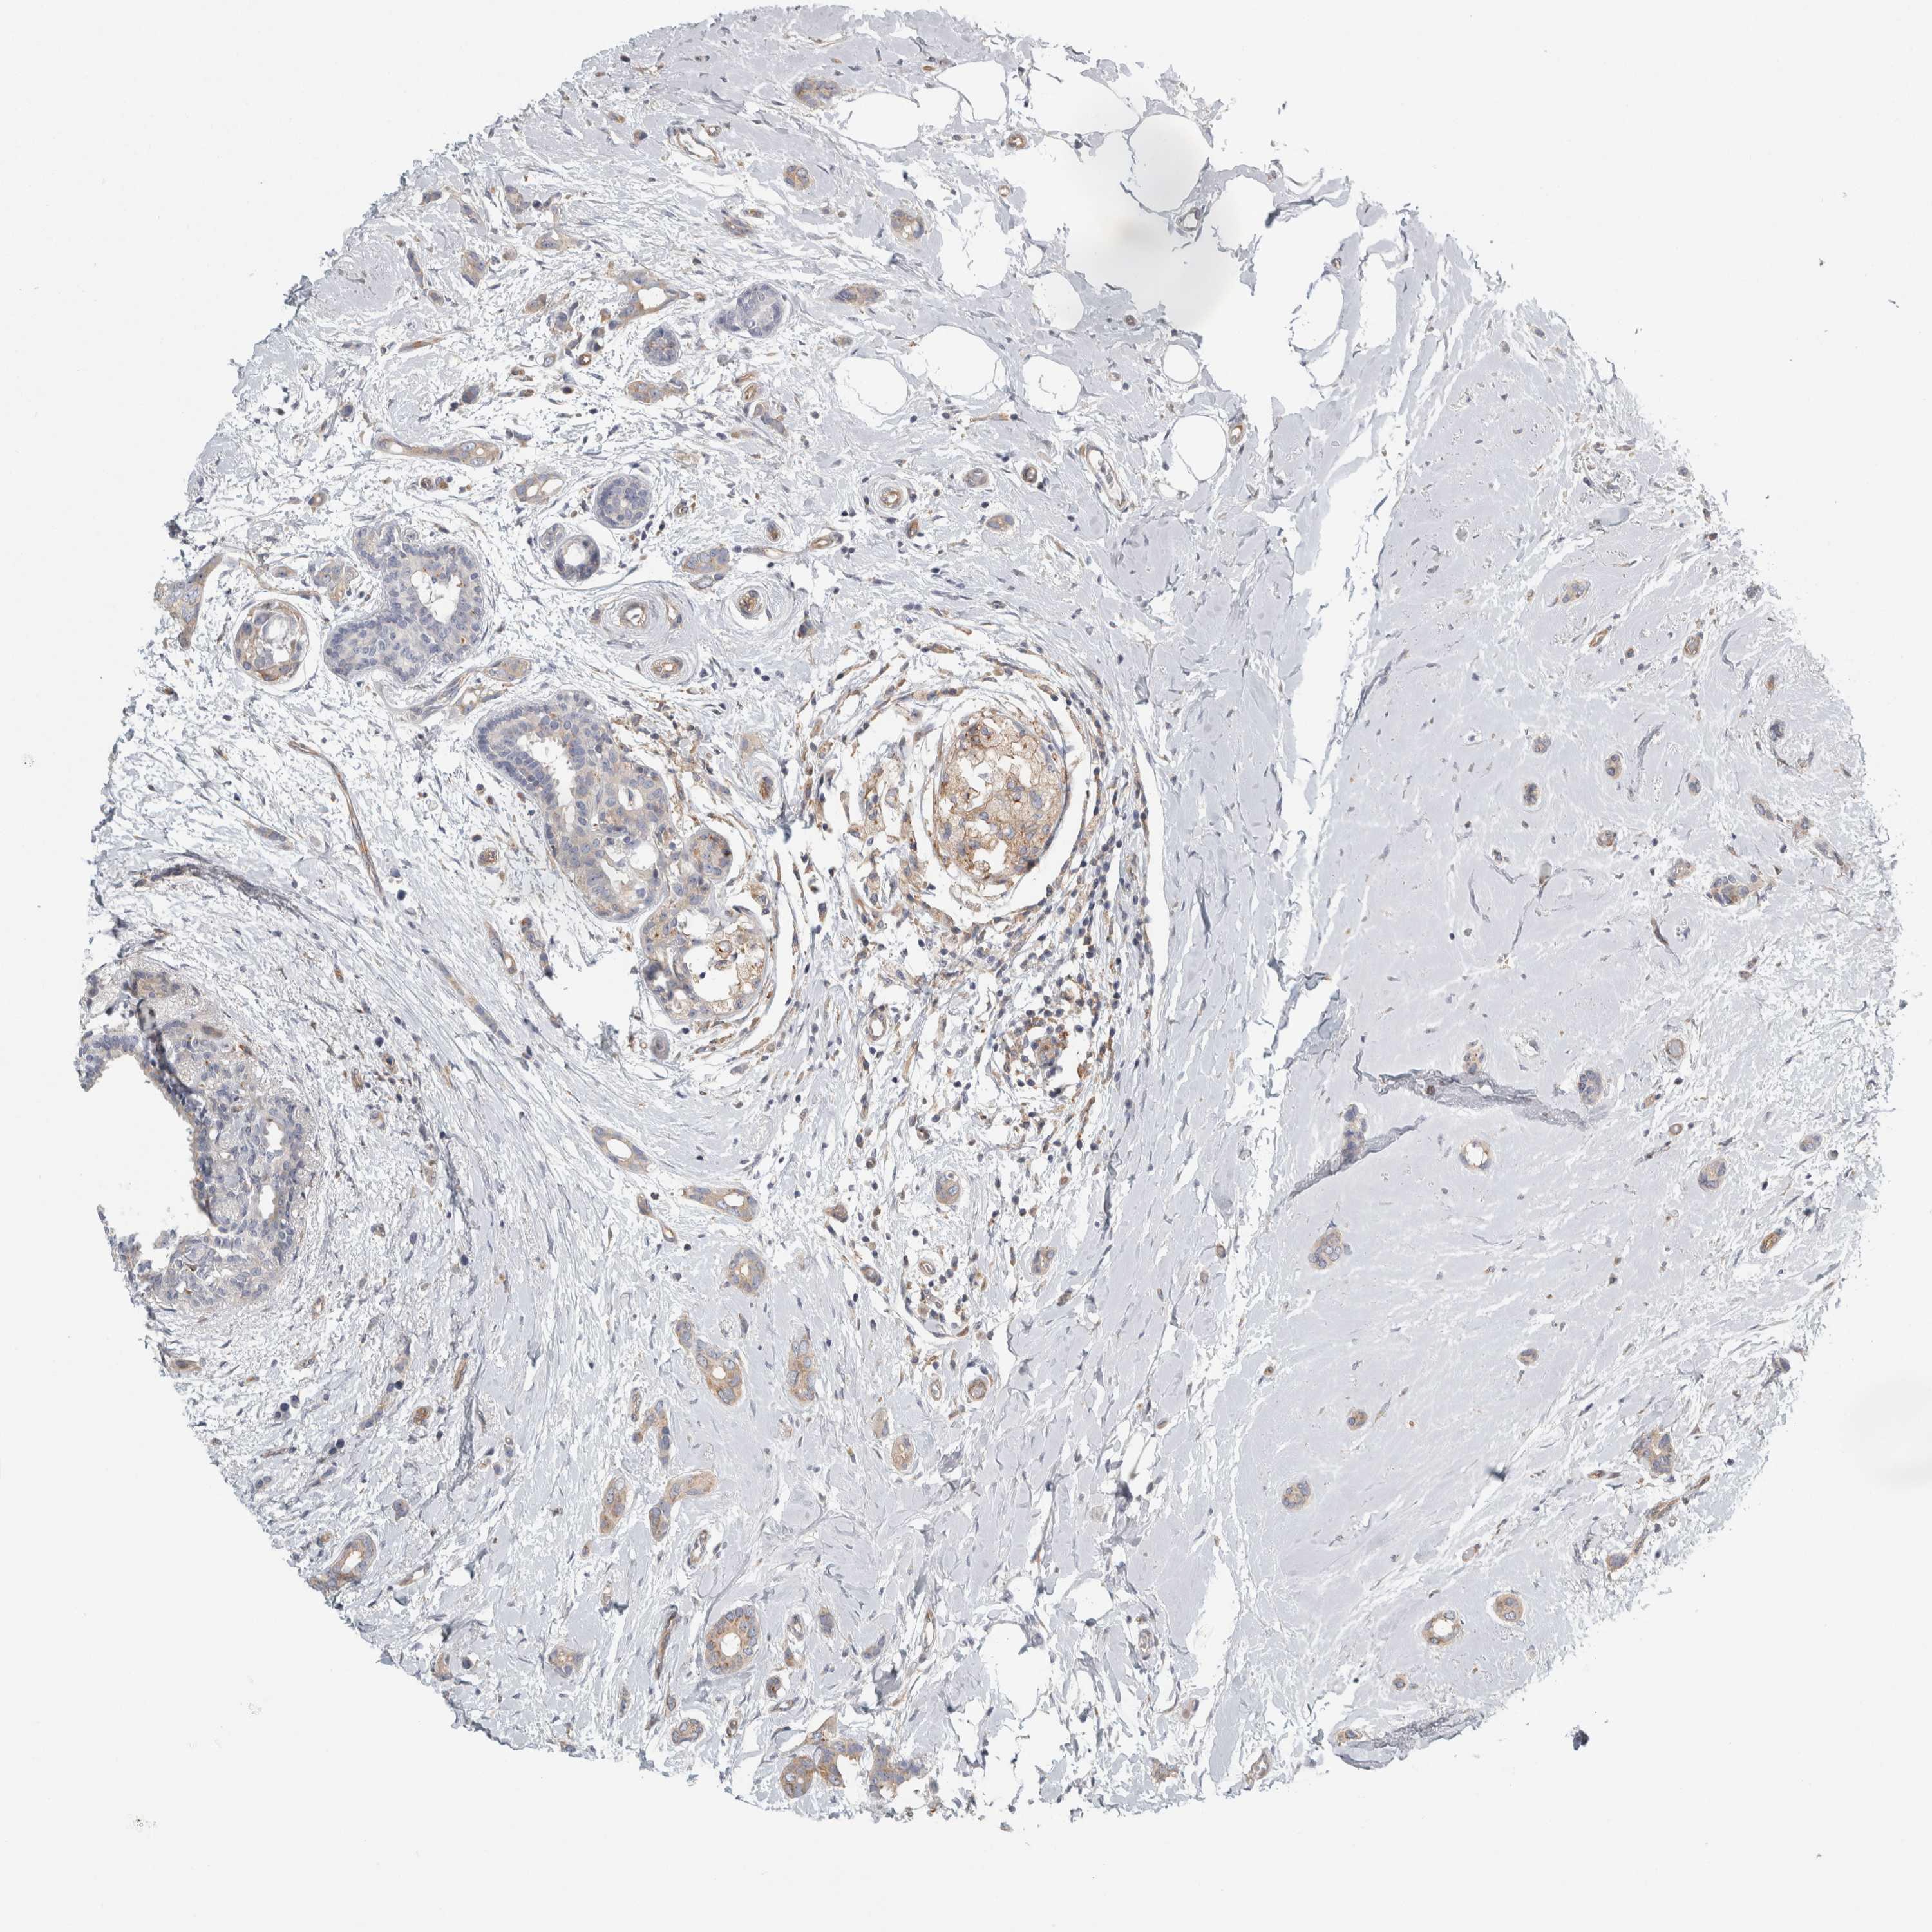

BRCA TCGA BRCA VALIDATION PROTEIN EXPRESSION

Breast cancer

Human cancer